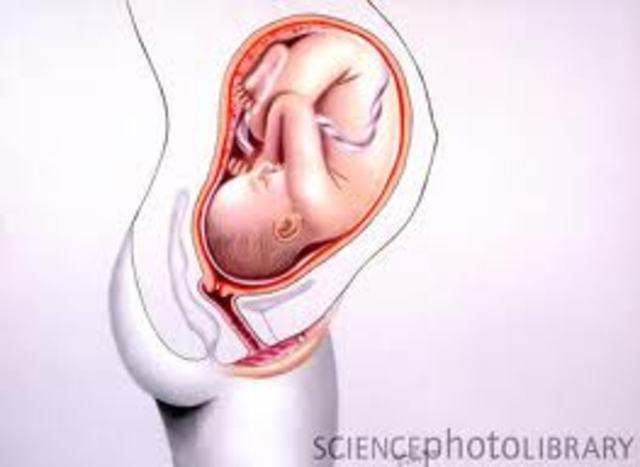

• Month nine - mom

Month nine - mom

"Lightening" felt as the fetus drops into the pelvis. Breathing becomes easier. Other discomforts may continue. A total weight gain of 25-35 pounds. False labor pains may be experienced.

• Month nine - baby

Month nine - baby

About 17-18 inch. Weight gain continues until the week before birth. Skin becomes smooth as fat deposits continue. Movements decrease as the fetus has less room to move around. Acquires disease-fighting antibodie from the mother's blood. Descends into tpelvis, ready for birth.